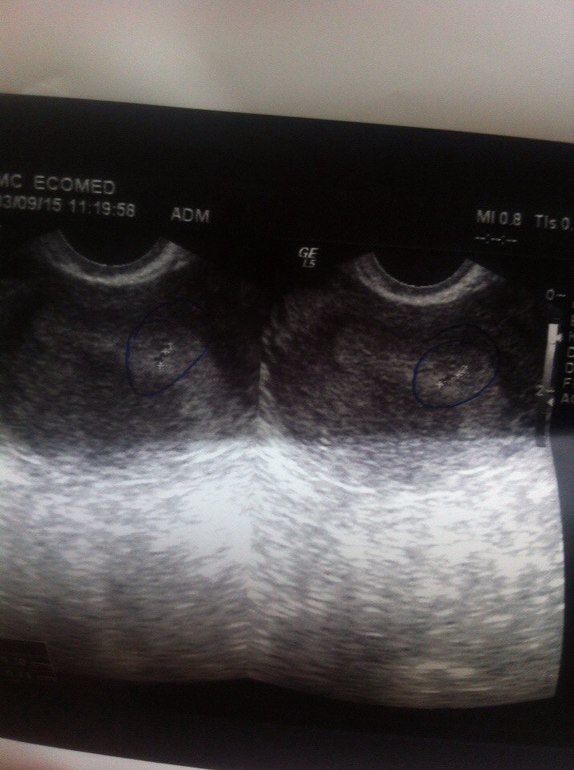

Вечером пришел ХГЧ - 188! Я была очень счастлива, лежала и молилась, чтобы всё обошлось. Утром побежала к врачу. Она оказалась просто потрясающей женщиной, успокоила меня, поболтала со мной. Сделала мне УЗИ. Прилагаю фото.

Сказала, что срок совсем маленький ещё и плодное яйцо всего 0.48 см. Сказала, что пишет бер под вопросом, т.к. размеры ну совсем малюсенькие. Выписала дюфастон, фембион и магне в6. Постельный режим, положительные эмоции и прийти к ней через неделю.

Ещё сказала такую вещь(может я её как-то не так поняла, объясните), что плодной яйцо должно располагаться ниже, у эндометрия, а у меня пока что оно не там, в матке, но не там, и надо ждать, пока он дойдет до нужного места. Это как так??